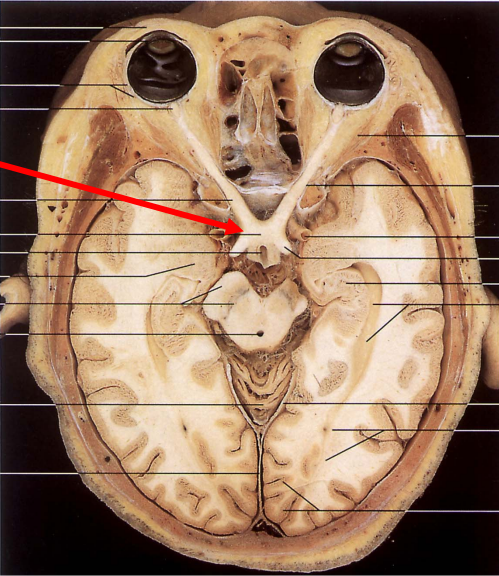

Describe the optic chiasm, including its location?

Fibres from right and left optic nerves combine to form optic chiasm

Lies at base of brain, anterior to pituitary, with internal carotid artery on either side

So, damage to the pituitary or internal carotid can affect the optic nerve and therefore vision